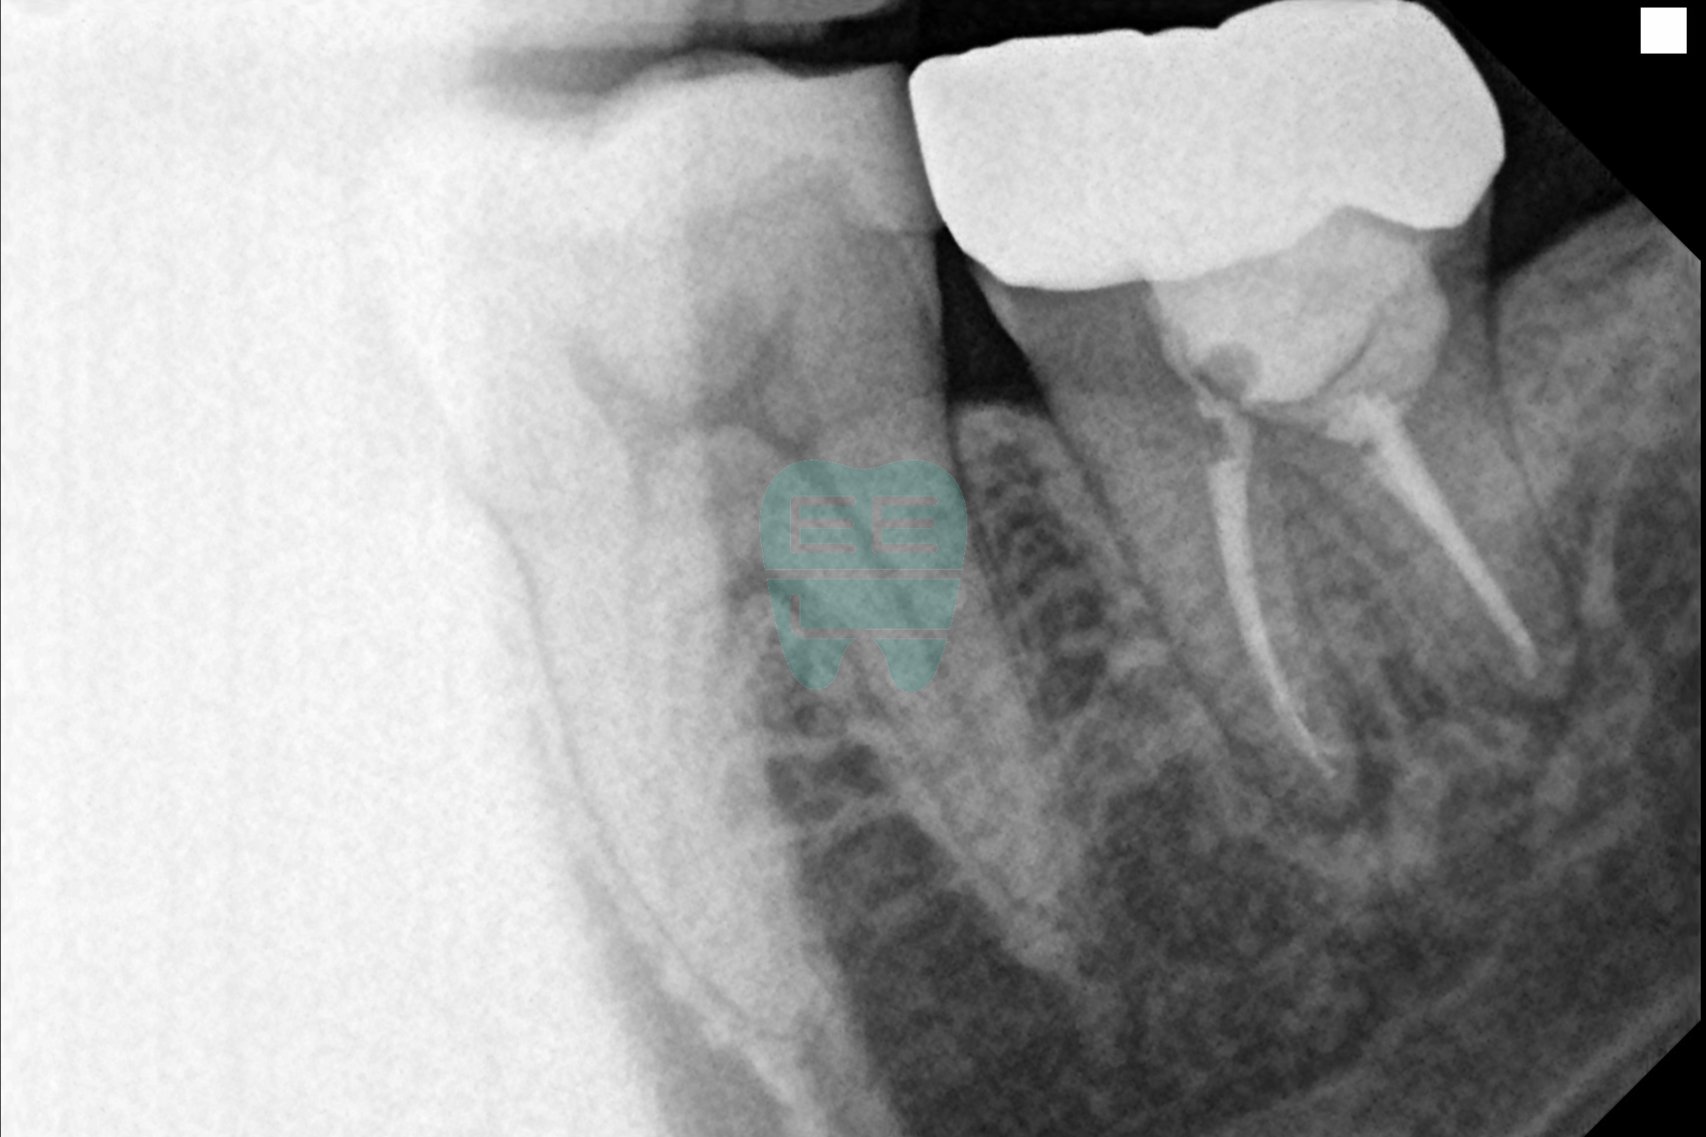

엑스레이 비교 (치료 전 vs 치료 후)

치료 후 엑스레이를 보시면, 기존에 문제가 되었던 부위가 깔끔하게 정리된 것을 확인하실 수 있습니다. 이후 재근관치료를 마무리하고 새로운 크라운을 제작하여 최종 수복을 진행할 예정입니다.